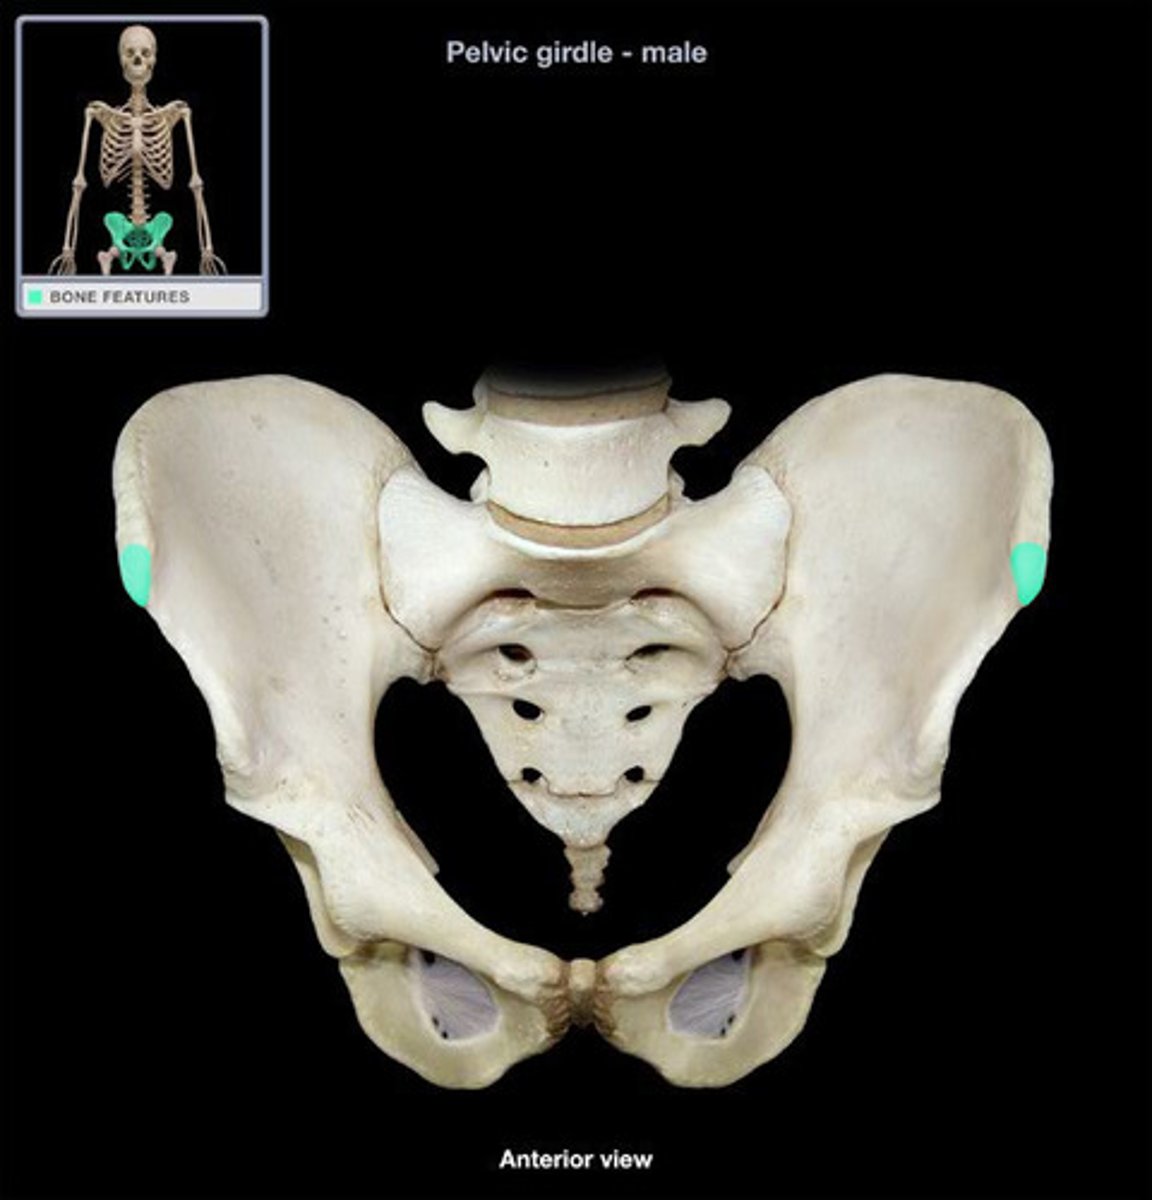

bony pelvis

2 coxal bones, sacrum, coccyx

ilium

weight bearing during sitting

pubis

The medial anterior portion of the pelvis

ischium

the lower, posterior portions of the pelvis

iliac crest

upper margin of iliac bones

posterior superior iliac spine

the sharp posterior end of the iliac crest

posterior inferior iliac spine (PIIS)

a bony projection located inferior to the posterior superior iliac spine

anterior superior iliac spine

origin of sartorius

anterior inferior iliac spine (AIIS)

origin of rectus femoris

iliac fossa

The broad, slightly concave inner surface of the ilium.

Acetabulum

large socket in the pelvic bone for the head of the femur

acetabular notch

deep notch in the inferior part of the brim

greater sciatic notch

allows blood vessels and the large sciatic nerve to pass from the pelvis posteriorly into the thigh

ischial tuberosity

receives the weight of the body when sitting

body of ischium

Makes up all of the ischium superior to the tuberosity

ramus of ischium

joins the inferior ramus of the pubis anteriorly

obturator foramen

opening in hip bone formed by the pubic and ischial rami

body of pubis

origin of adductor longus

arcuate line

a ridge of bone that runs inferiorly and anteriorly from the auricular surface, forms pelvic brim

iliopubic eminence

marks the point of union of the ilium and the pubis just lateral to the arcuate line

pubic tubercle

An attachment point for the inguinal ligament.

superior ramus of pubis

origin of pectineus

inferior ramus of pubis

origin of adductor brevis

pubic symphysis

cartilaginous joint at which two pubic bones fuse together